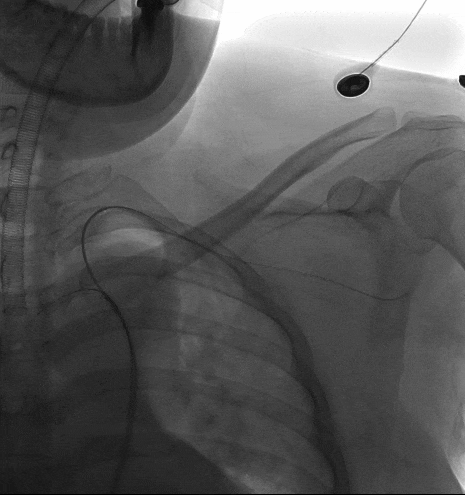

1、患者平躺后行全身麻醉手术,穿刺患者左肱动脉与右股动脉,并在左肱动脉置入穿刺鞘后,从右股动脉导入一根长鞘,长鞘里同走超硬导丝与软泥鳅导丝,自下而上地探索真腔,在软泥鳅导丝穿出左肱动脉后,完成左肱动脉-右股动脉的导丝通路建立后,从左肱动脉导入导引导管,接着在右股动脉交换泥鳅导丝为分支导丝,完成分支导丝通路建立,然后从右股动脉长鞘内并行导入造影导管至升主动脉,进行术前造影,确认患者为B型主动脉夹层。

长鞘走双导丝,泥鳅超选LSA

动脉长鞘怎么置入宁波市第二医院血管外科运用Castor®单分支支架结合长鞘建立导丝通路的方法治疗Stanford B型胸主动脉夹层一例_https://www.jmylbn.com_新闻资讯_第7张

术前DSA造影